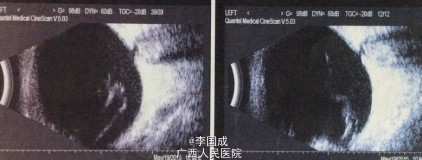

眼部检查: 视力:VOD:0.6 ,VOS:无光感,IOP:OD 34 mmHg,OS 19 mmHg,右眼无充血,角膜清,角膜背可见成簇状色素性kp,中央前房深度4CT,周边1/3CT,闪辉+,虹膜弥散萎缩,纹理欠清,虹膜后粘连,瞳孔对光反射—,晶体混浊,眼底窥不清。左眼无充血,角膜清,中央前房深度4CT、周边1/3CT,闪辉+,瞳孔对光反射-,欠圆,虹膜瞳孔缘后粘连,虹膜周边房角不规则前粘连,晶体混,眼底窥不清。 房角:双眼NⅣ(全粘闭)。

1.双眼葡萄膜炎继发性青光眼 2.左眼绝对期青光眼 3.双眼并发性白内障 4.双眼慢性葡萄膜炎 5.双眼瞳孔闭锁 处理:右眼小梁切除术+前房形成术+虹膜部分切除术+瞳孔粘连松解术

右眼视力0.5眼压25mmHg,充血,角膜雾状水肿,前房闪辉++,滤泡稍扁平,缝线在位。虹膜部分后粘连,晶体混。 左眼无充血,角膜清,前房清,角膜kp+,瞳孔区虹膜后粘连,虹膜膨隆,晶体混。 讨论: 小梁切除术术中联合应用MMC、粘弹剂、虹膜前后粘连分离、虹膜节段切除及可控缝线技术能够提高较严重葡萄膜炎继发性青光眼的手术成功率,减少手术并发症及术后炎症反应。减少葡萄膜炎复发。